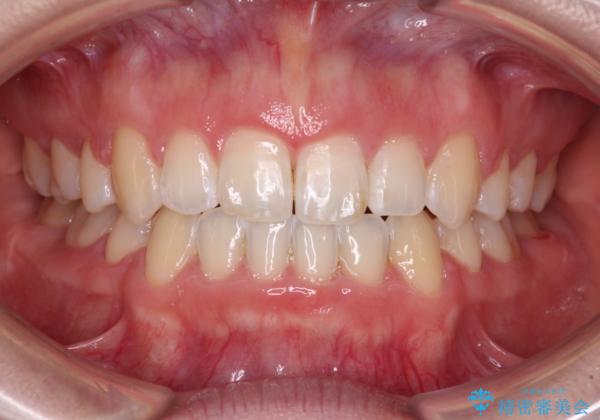

- 口元の突出感と口の閉じにくさ、前歯のデコボコを気にして来院された患者様です。

上下左右第一小臼歯4本を抜歯し、ワイヤー装置にて口元を引っ込めるよう矯正治療を行うこととしました。

骨格的に下顎骨が前方位にあるため、口元の突出感改善には限界があると思われましたが、唇の閉じにくさが改善するほど引っ込めることができました。